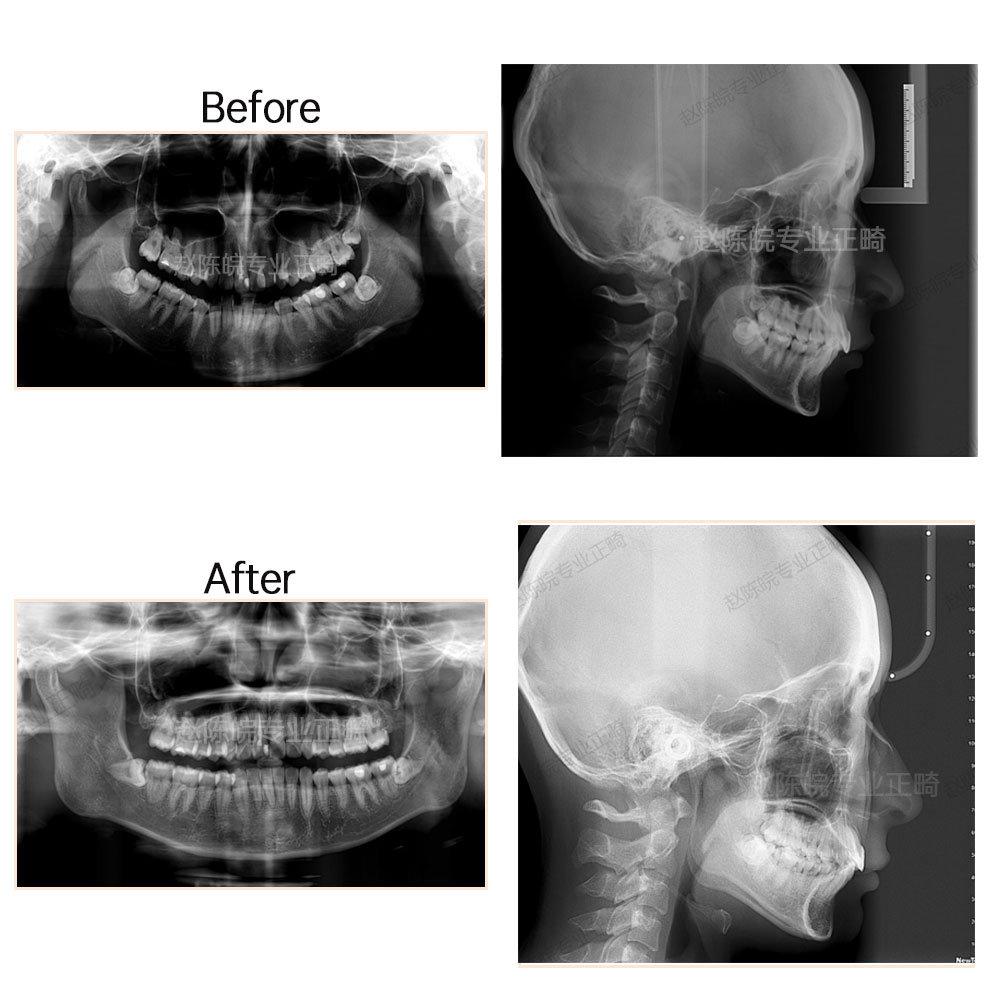

?矯正前后X線片前后對比圖(觀察對比側(cè)面顱骨情況及牙體牙周情況)

完成結(jié)果:達到矯治目標,牙列排齊,中線就真正,咬合中性,覆合覆蓋正常。